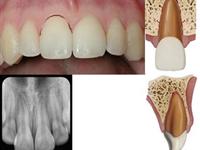

牙髓对于牙齿来说是很重要的一个组织,牙齿需要靠牙髓提供氧气和营养物质,但是因为各种原因会造成牙髓的坏死,这样就会影响到牙齿的正常工作了。

第一:牙髓之所以会坏死,有一部分的原因是因为人们在生活中没有小心的保护牙髓,例如,平时的时候不小心让牙齿受到外伤了,这些外伤是会影响到牙髓的,会造成牙髓的坏死的。

第二:牙髓对于牙齿来说有着那么重要的地位,有些人牙齿出现了一些问题,就会到医院里面去洗牙齿或者是用一些化学物质,其中有一些化学物质会刺激牙髓,导致牙髓坏死的。

第三:有些人平常没有注意保护好自己的牙齿,导致牙齿出现了龋齿,出现了龋齿,就会选择补上漏洞,在修补的过程中,会添加上一层的物质,这个物质中含有的成分就会影响牙髓坏死。

注意牙髓坏死的原因,及时的保护好牙髓,不让其受到伤害。